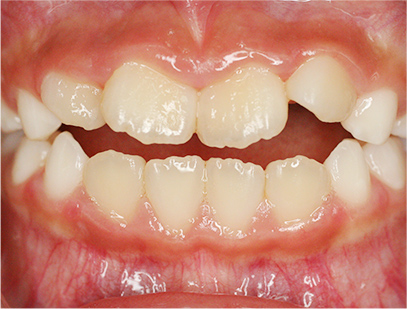

前歯部の開咬とデコボコ

前歯部が咬んでいないことを主訴として来院されました。精査、診断の結果「前歯部にデコボコを伴う開咬」と診断されました。

下の歯の裏側に舌が出ないように矯正装置を取り付け、そして上の歯には取り外しのできる矯正装置を装着して、側方に拡大を行います。

取り外しのできる矯正装置、舌が出せなくなる矯正装置(フェンス)